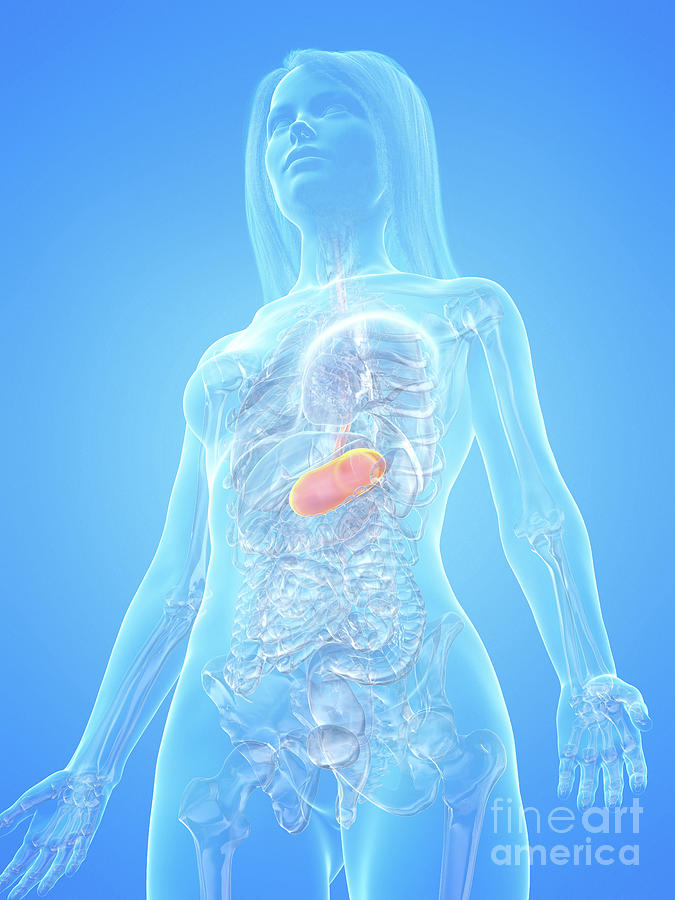

From fineartamerica.com

Human Stomach Photograph by Sebastian Kaulitzki/science Photo Library Can A Human Stomach Explode One person died from tearing their oesophagus, the tube that connects the mouth to the stomach and others have actually ruptured their stomach by. burping can be gross, but imagine the chaos if all of that gas built up in your stomach. but what you’re probably wondering is: While theoretically possible, it is extremely unlikely for your stomach. Can A Human Stomach Explode.